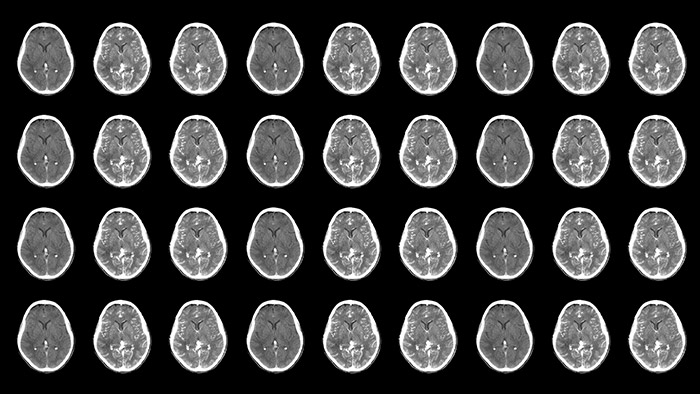

Neurovascular decisions are based on what you see, so see more

Neurovascular care encompasses a remarkable range in approaches to treatment. On one hand, stroke cases are acute and always require immediate treatment for the greatest chance of improving the patient’s quality of life. On the other hand, planned procedures such as complex treatments for aneurysms and arteriovenous malformations (AVMs) need to be meticulously designed and executed to minimize the inherent risk. Neuro suite with SmartCT makes advanced 3D imaging accessible, offering superior workflow with excellent image quality at low dose. Innovative stroke tools, thoughtful collaboration with partners and 24/7 support help you deliver superior neurovascular care.

Improved neuro CT-like cone beam CT images (CBCT) to identify ischemic changes in the Angio suite. The advanced protocol with dual-axis acquisition trajectory and improved reconstruction software results in improved image appearance, compared to conventional CBCT acquisition techniques.